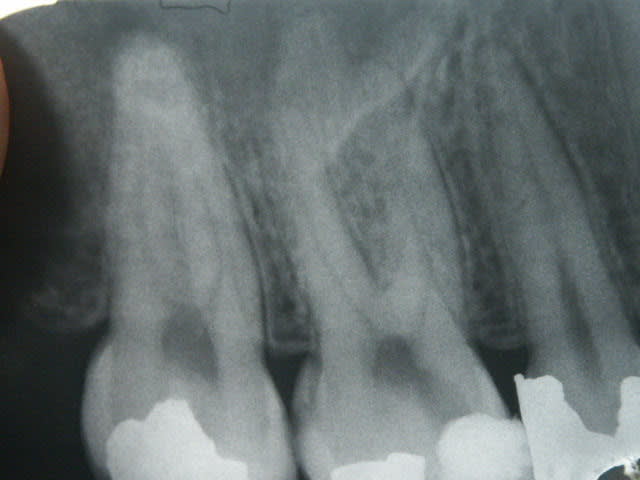

Petit endo du jour (16, 4 canaux) sur une jeune patiente (17 ans) souffrant de polycaries. J'ai entrepris un questionnaire alimentaire et une correction des mauvaises habitudes avant de me lancer dans les soins. Tout est à faire ou à refaire. Il y a une bonne quinzaine de dents à soigner, le reste est à surveiller avec beaucoup d'attention! Elle se goinfre de cochonneries avec ses copines à l'internat...

Sur un(e) patient(e) de cet âge, les 4 canaux, c'est presque bingo dans 100% des cas même si le MV2 est toujours plus difficile à trouver.

Sur la racine palatine, la fusée de ciment me fait repenser un peu au sapin de noël... :-)))

Superbe endo !

Comment fais-tu pour obtenir une telle préparation ? Protaper uniquement où ajoutes-tu d'autres instruments dans la séquence (gates ?) ?

J'ai la même sensation que Chap, et mes préparations apicales ne donnent pas l'image de la radio de tonio.

Dans ce cas, le MV1 a été préparé à la LT au F2, le MV2 au F1, le DV au F3, le P au diamètre 40 (finition manuelle car pas encore de F4 ni de F5 au cabinet).

Je ne me fixe jamais de diamètre minimum de préparation puisque ce qui compte c'est la conicité apicale (qui assure la circulation de l'irrigation) qui est doit être au minimum de 6% pour être suffisante. Avec le F1, on est déjà à 7%.

Donc comme le dit très justement (pour une fois... ;-) ) Bjorn, si la LT nous indique de préparer à 20, on prépare à 20. Garder un foramen étroit est aussi un des objectifs à remplir. Cela n'empèche pas d'obtenir une perméabilité apicale salvatrice (cf. micro-puffs sur la racine MV).